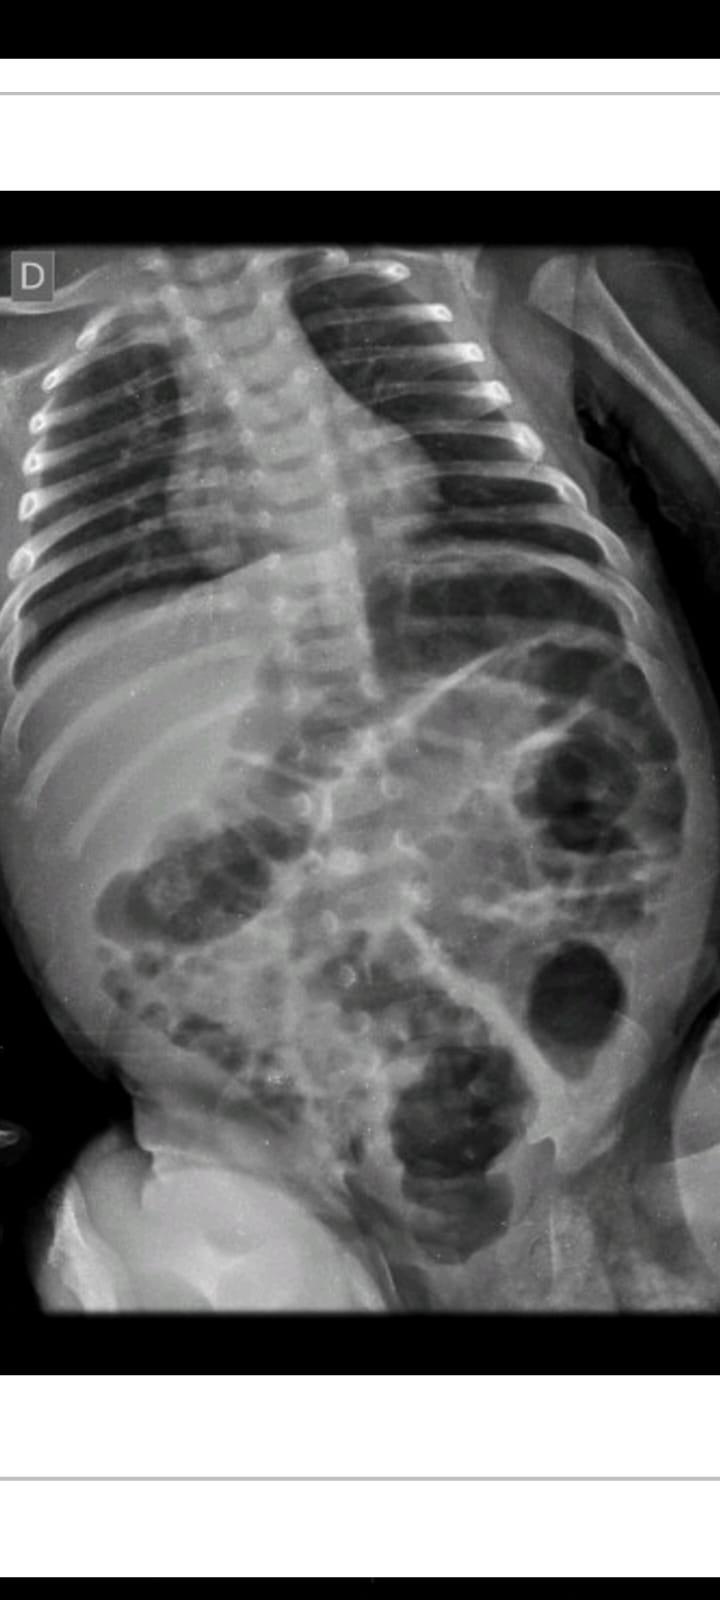

Na manhã desta segunda-feira (07) a 20ª Subdivisão Policial de Toledo divulgou o resultado das investigações acerca de uma tentativa de homicídio praticada contra um bebê, na época com aproximadamente 40 dias, onde os pais do infante eram os suspeitos.

O caso ocorreu no início do mês de julho, sendo os pais investigados inicialmente presos temporariamente por 30 dias.

Durante este período as investigações transcorreram e foi possível reunir ainda mais evidências do envolvimento dos pais da criança no caso, fato este que ensejou representação pela Prisão Preventiva, a qual foi determinada pelo Poder Judiciário, seguindo os pais da criança (21 e 22 anos de idade) agora presos por tempo indeterminado enquanto aguardam o andamento do Processo.

O Delegado Rodrigo Baptista Santos disse que "a postura dos investigados em sustentar uma versão absurda para os fatos constatados, dizendo que não tinham notado os hematomas, os quais surgiram repentinamente, acreditando serem reações alérgicas de uma picada de mosquito, caíram por terra com os Laudos e exames que atestam a gravidade das lesões e o risco a vida do qual o infante foi exposto".